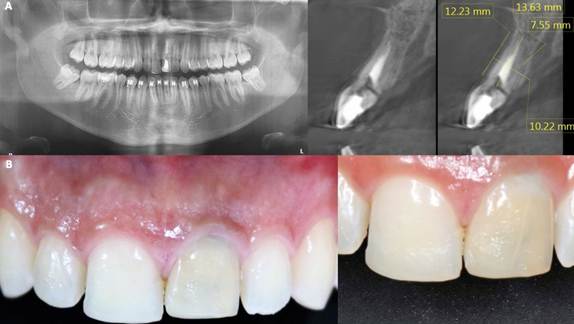

A 24-year-old male patient who required extraction of the upper left central incisor due to a corono-radicular fracture, reason for which is requested, panoramic radiography and cone beam, in which, as in the immediately previous case, the extraction was planned using a two-armed lever as an atraumatic alveolar preservation technique. During the clinical examination, it was observed at the level of the upper left central incisor, resin filling of 4 surfaces and slight redness was evident at the gingival margin (Figure 3.A and Figure 3.B). The extraction procedure was initiated by applying the strength of the two-arm lever, the straight elevator is in a horizontal position resting on the mesial and distal surfaces have the greatest possible palatal rest and resistance in the mesial and/or disto-vestibular areas; that generates an extrusive dental dislocation that combined with the vestibular palatine grip with the left hand helps to avoid compromising the vestibular table, then it is produced in the first instance, tooth crown extraction (Figure 4.A and Figure 4.B), by the corono-radicular fracture already mentioned, then its proceed to the dental root´s extraction, using lever of the second degree, without compromising the vestibular and palatal tables. Once confirmed the integrity of the vestibular wall and the gingival biotype: type I socket, 1cc of Puros® particulate cortical bone (250-1000 microns) is used for the graft. Subsequently, Zimmer TSV 3.7 * 13mm implant was placed (Figure 5). The implant was prepared and placed 2.5mm from the gingival margin to achieve primary fixation, a surgical cover screw was placed, the cavity was occluded with a collagen membrane (CollaTape®) and sutured transverse and horizontally with acid polyglycolic 5-0, followed by a provisional restoraion, finally, the patient is prescribed oral capsules of dicloxacillin 500mg and nimesulide tablets orally 100mg. After five months of clinical and radiographic controls, the second phase begins. The patient received a metallic ceramic crown with functional and aesthetic results after 18 months of continuous controls.